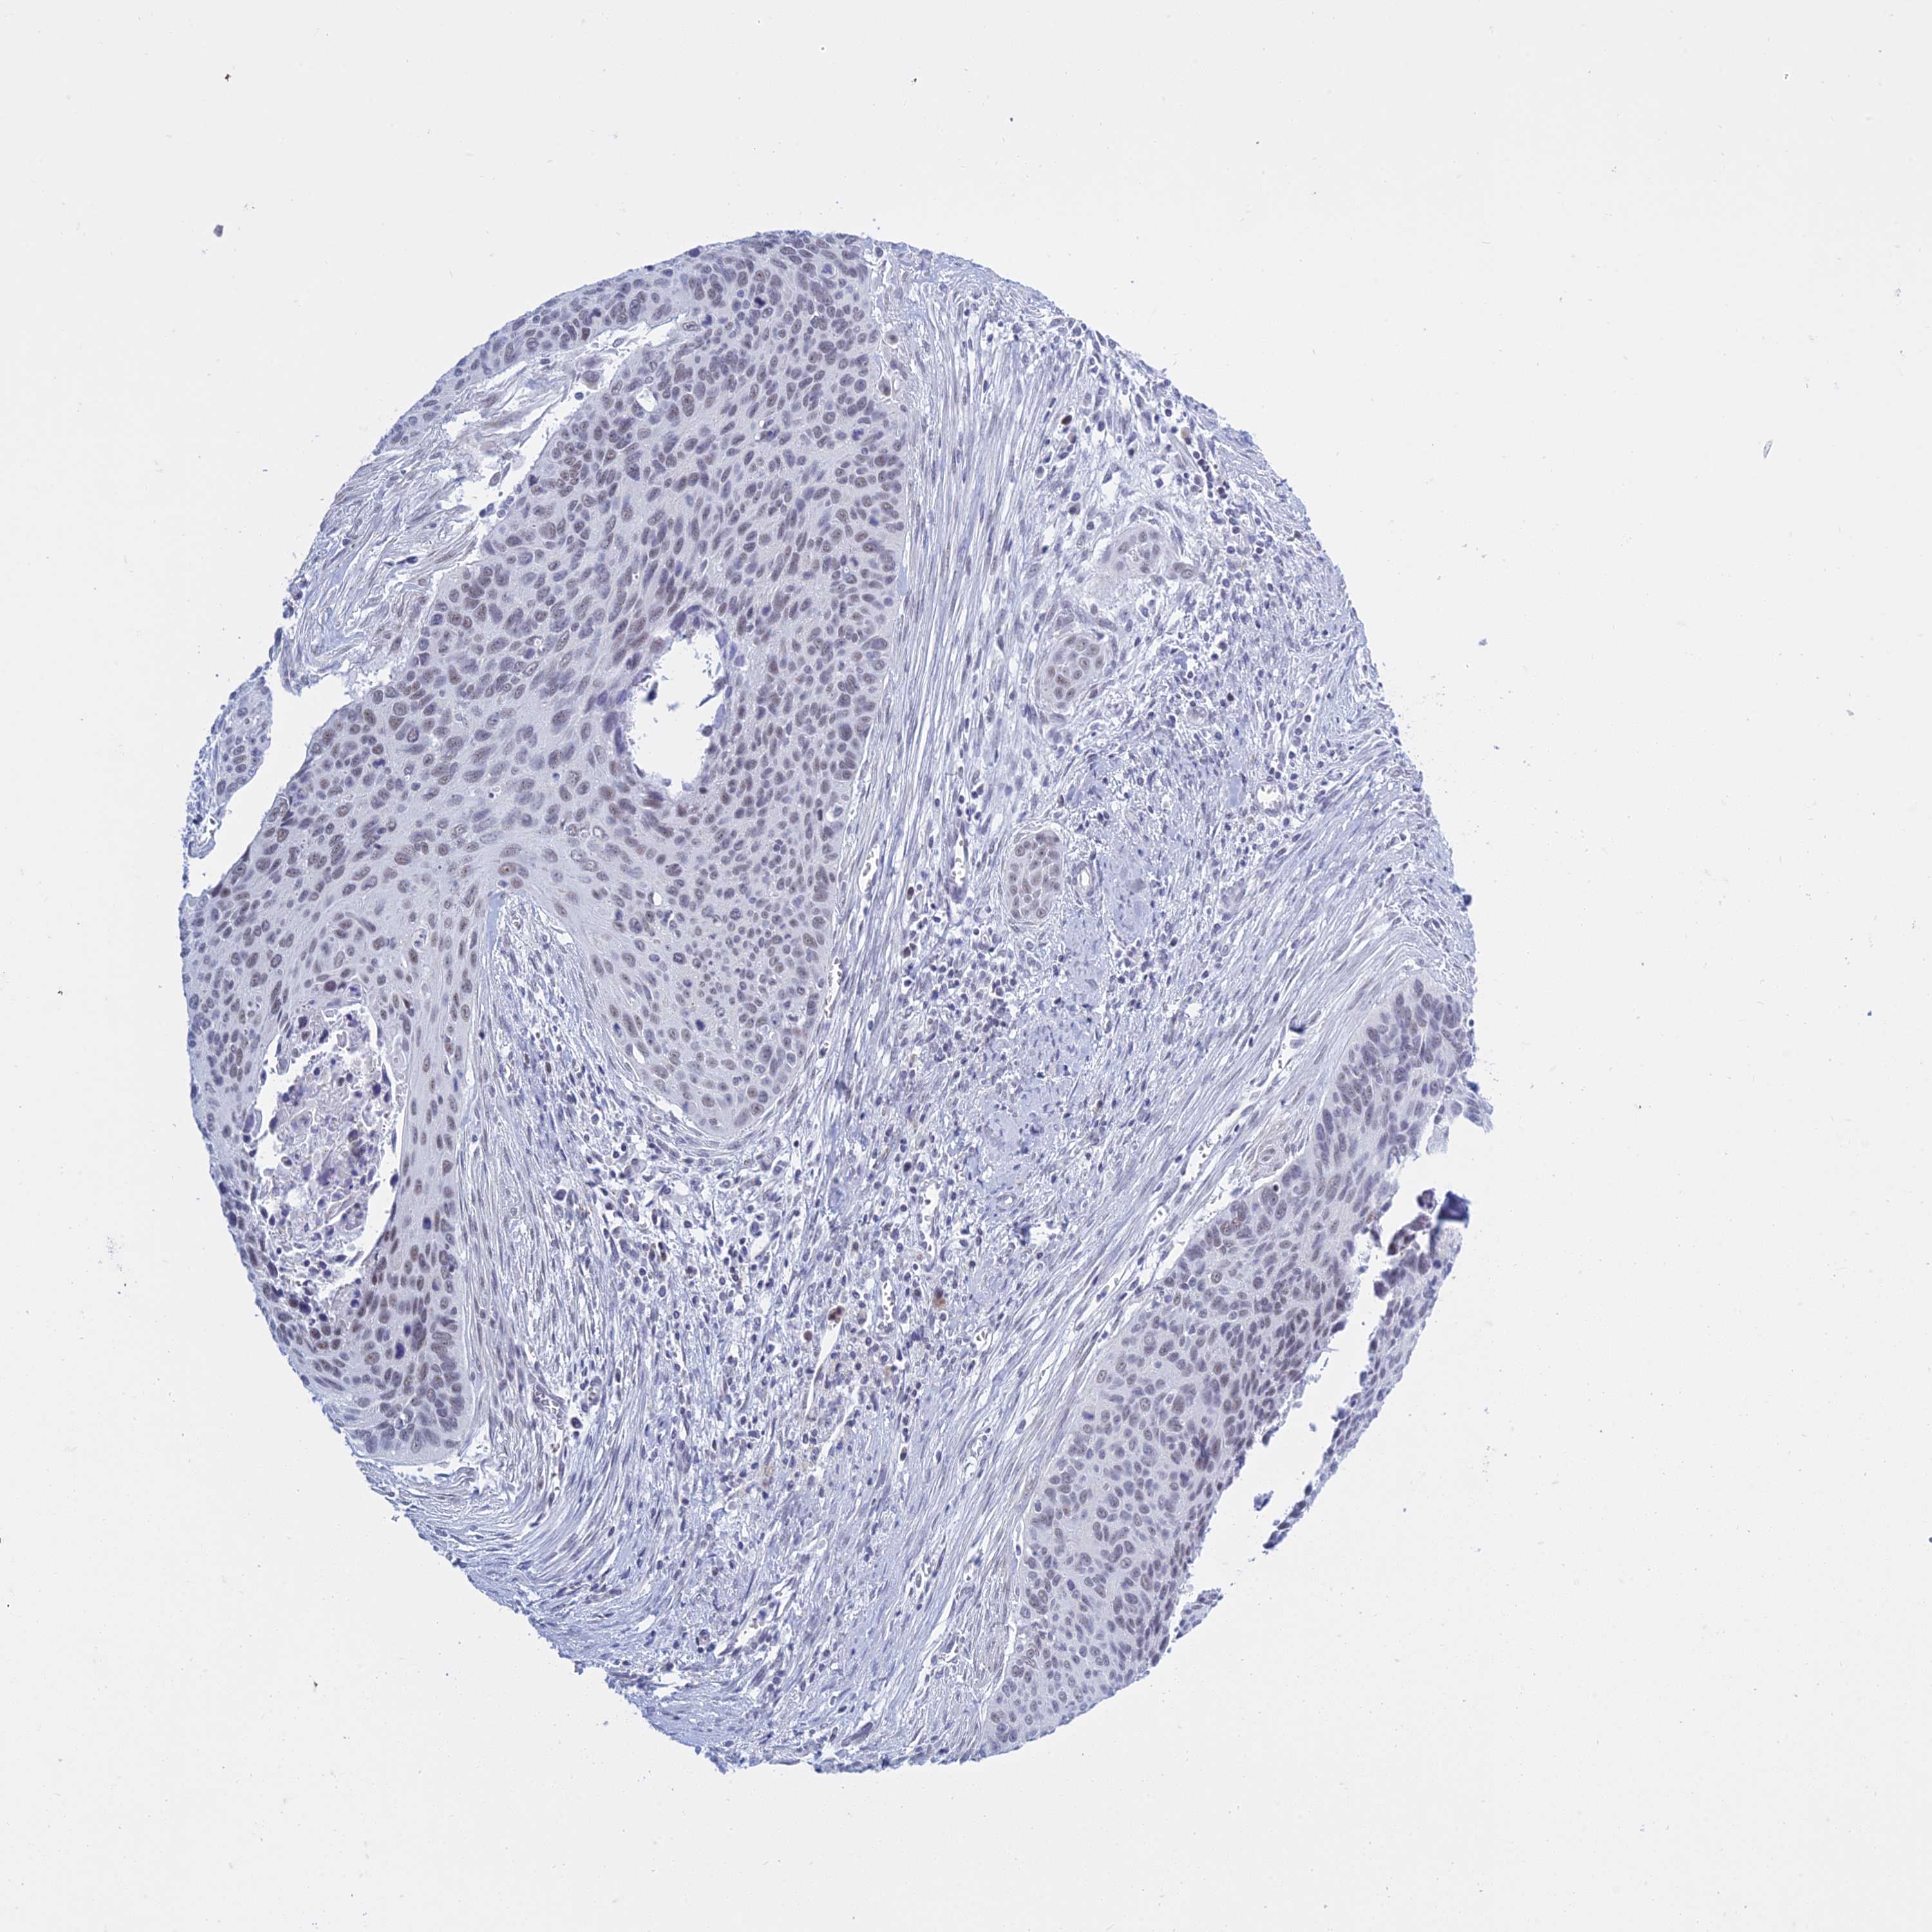

CERVICAL CANCER - Protein expressioni

A mouse-over function shows sample information and annotation data. Click on an image to view it in a full screen mode. Samples can be filtered based on level of antibody staining by selecting one or several of the following categories: high, medium, low and not detected. The assay and annotation is described here.

Note that samples used for immunohistochemistry by the Human Protein Atlas do not correspond to samples in the TCGA dataset.

Antibody stainingi

Antibody staining in the annotated cell types in the current human tissue is reported as not detected, low, medium, or high, based on conventional immunohistochemistry profiling in selected tissues. This score is based on the combination of the staining intensity and fraction of stained cells.

Each image is clickable and will lead to virtual microscopy that enables deeper exploration of all samples and also displays staining intensity scores, fraction scores and subcellular localization as well as patient and tissue information for each sample.

Antibody HPA044729

Staining

High

Medium

Low

Not detected

Intensity

Strong

Moderate

Weak

Negative

Quantity

>75%

75%-25%

<25%

None

Location

Nuclear

Cytoplasmic/membranous

Cytoplasmic/membranous,nuclear

Squamous cell carcinoma, NOS

Adenocarcinoma, NOS